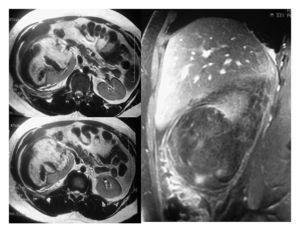

Una vez en mejor estado general se realizó tomografía axial computarizada que mostró una imagen de un tumor renal derecho de 10 UH heterogéneo que desplazaba en sentido posteroinferior y medial al riñón (Imagen 1). Las dimensiones del tumor fueron de 15 cm en sentido longitudinal y 10 cm en sentido transversal, de características heterogéneas con un refuerzo de -30 UH al administrar medio de contraste, lo que aumentó la sospecha de angiomiolipoma renal. Se realizó resonancia magnética con reconstrucción vascular, en la cual se observó hiperintensidad en T1, isointensidad en T2, sin delimitar el tumor y con sangrado con dimensión aproximada de 6-7 cm de diámetro (Imagen 2). En la angiorresonancia se observó pobre vasculatura, incrementando la sensibilidad diagnóstica para angiomiolipoma (Imagen 3).

Imagen 2. RM fase T1 y T2.